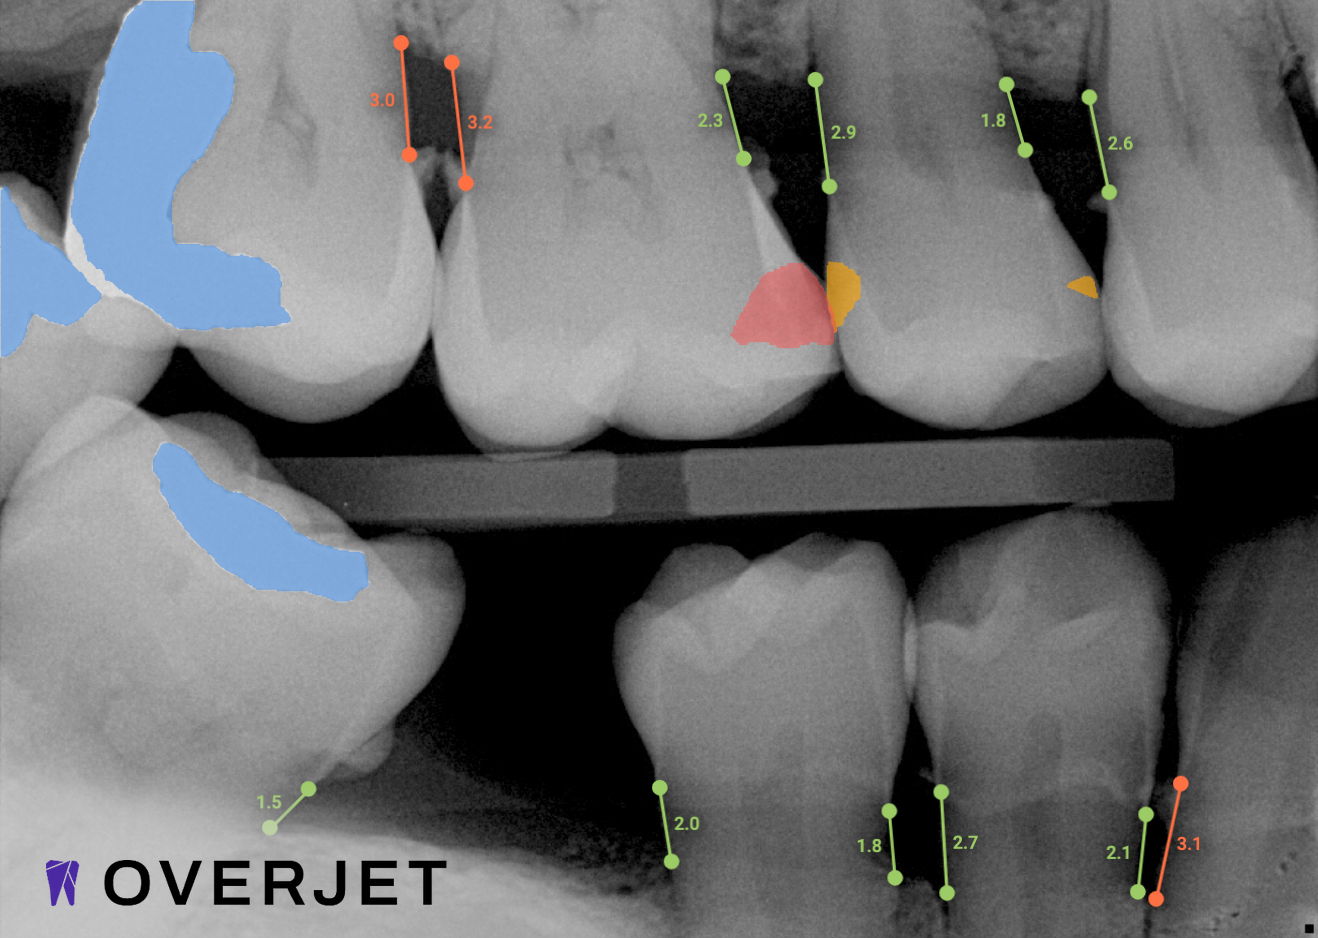

See More with AI

Overjet AI's  patient-centric technology combines human intelligence with the power of artificial intelligence.

Overjet’s artificial intelligence technology transforms traditional black-and-white X-rays by adding a layer of data that instantly outlines decay (cavities) and measures bone loss. This makes it easy for you to see your results alongside your dentist.  It’s like getting a second opinion delivered instantly. With Overjet’s analysis and easy-to-read presentation, you will have the information you need to make an informed decision about your oral health. Together, we’ll review your findings and discuss the best steps to take to achieve your goals.